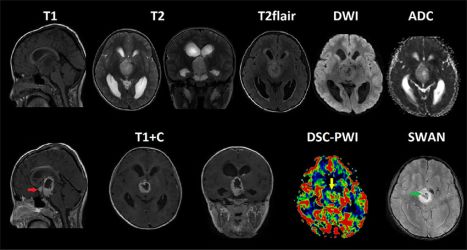

МРТ головного мозга и DSC-перфузия. Крупное отчетливо отграниченное образование, локализованное в гипоталамической области, с распространением в 3й желудочек (с признаками окклюзии последнего, вызывая бивентрикулярную гидроцефалию), межножковую и предмостовую цистерны. На постконтрастных T1-ВИ отмечается выраженное, относительно гомогенное контрастирование опухоли с зоной центрального некроза и наличием единичного узелка отсева в область хиазмы (красная стрелка), кроме того визуализируется сеть патологически расширенных сосудов и наличие микрокровоизлияний на ИП SWAN (зеленая стрелка). На перфузионных картах образование демонстрирует неоднородное повышение значений rCBV вокруг некроза (желтая стрелка) без видимого ограничения диффузии.

Высокие значения ADC могут быть использованы в качестве надежного фактора , указывающего на низкую клеточность пилоцитарных астроцитом. Повышение перфузионных показателей rCBV демонстрируют худшие диагностические критерии и являются не патогномоничными, поскольку пилоцитарные астроцитомы очень часто отражают высокие значения rCBV, таким образом имитируя опухоли высокой степени злокачественности. Вазогенный отек встречается редко - эта особенность так же является ценным ключом в постановке диагноза.